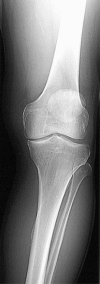

The orthopaedic approach to managing osteoarthritis of the knee